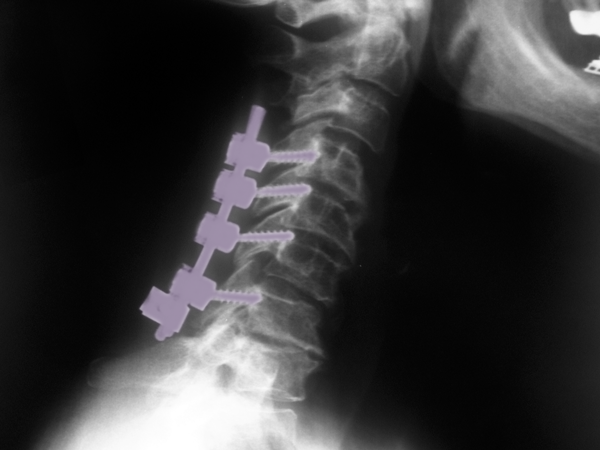

Περιγραφή Η οπίσθια αυχενική σπονδυλοδεσία πραγματοποιείται υπό γενική αναισθησία και με τον ασθενή σε πρηνή ή καθιστή θέση. Η τομή του δέρματος γίνεται στο μέσο του αυχένα και κατόπιν παρασκευάζονται τα οπίσθια στοιχεία της σπονδυλικής στήλης. Η σταθεροποίηση του αυχένα γίνεται με τη βοήθεια συστήματος με βίδες και ράβδους. Οι βίδες τοποθετούνται ή στα πλάγια ογκώματα ή στους αυχένες των αυχενικών σπονδύλων που πρόκειται να συνδεθούν, υπό ακτινοσκόπηση, και οι κεφαλές τους συνδέονται με ράβδους ενώνοντας με αυτό τον τρόπο τους σπονδύλους που χρήζουν σταθεροποίησης. Η τοποθέτηση των βιδών ακολουθείται, όταν αυτό απαιτείται, από πεταλεκτομή. Η ινιοαυχενική σπονδυλοδεσία διαφέρει στο ότι στη σπονδυλοδεσία συμπεριλαμβάνεται και το ινιακό οστό, στο οποίο επίσης τοποθετούνται βίδες και αυτές ενώνονται μέσω ράβδων στις βίδες των αυχενικών σπονδύλων σταθεροποιώντας έτσι και την ινιοαυχενική άρθρωση. |

Οπίσθια αυχενική πεταλεκτομή και σπονδυλοδεσία Α4-Α7. |